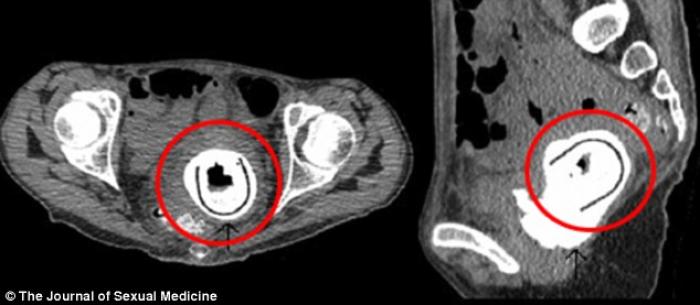

O femeie în vârstă de 38 de ani a ajuns la spital plângându-se de mari pierderi în greutate și letargie. Este vorba despre o doamnă din Scoția care a stat cu o jucărie sexuală de 12,7 cm în interior, timp de 10 ani.